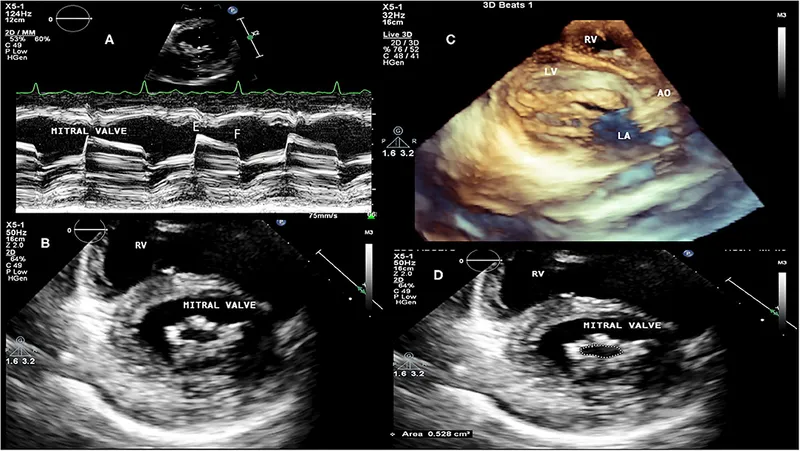

- Echocardiography (2D Echo & Doppler): Gold standard. Confirms diagnosis, assesses valve damage & function.

- Common Valvular Lesions (Echo findings):

- Acute Phase:

- Mitral Regurgitation (MR): Most common (📌 Carey Coombs murmur).

- Aortic Regurgitation (AR).

- Valvulitis: Annular dilatation, leaflet edema, prolapse, chordal elongation.

- Chronic Phase:

- Mitral Stenosis (MS): Most frequent. "Fish-mouth" valve.

- MR, AR, Aortic Stenosis (AS).

- Thickened, fibrosed, calcified leaflets; chordal fusion.

⭐ Mitral valve is the most commonly affected valve in chronic RHD, typically leading to mitral stenosis.